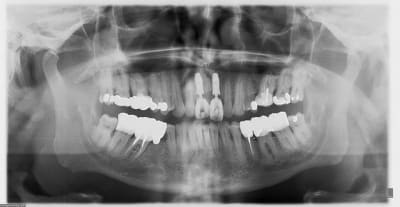

une série de photo le jour de la pose, puis 15j après (prothèse réalisée par mon confrère)

Img 3018 rccxu5 - Eugenol

Img 3019 opg6a4 - Eugenol

Img 3020 cfor6c - Eugenol

Img 3031 xzaslk - Eugenol

Img 3032 jojp8s - Eugenol

Pano u7x6bm - Eugenol